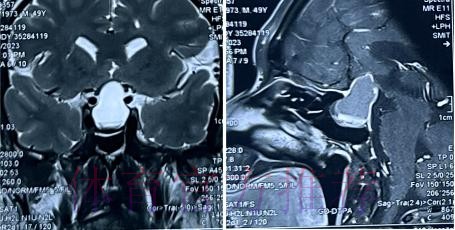

从恐慌到冷静 影像学检查给出的真实答案

在高速对抗的现代足球里 现场肉眼和赛后情绪往往会放大对伤情的判断 一名球员倒地呻吟或无法坚持比赛 很容易被解读为韧带断裂 或肌肉严重撕裂 但真正决定恢复周期的关键因素 通常要到核磁共振检查之后才会明朗 因为核磁能在较早阶段清晰显示软组织 肌肉 韧带以及骨结构的微小损伤情况 对伤情做出更接近真相的分级判断 塞巴略斯此次就是典型案例 初步观感可能让人联想到更严重的伤病 但核磁提示伤情相对可控 没有出现完全断裂或大面积撕裂 也就意味着他不需要漫长的康复旅程 只要遵循医学建议 科学负荷管理 就有机会用较短的时间重新回到训练场和比赛中